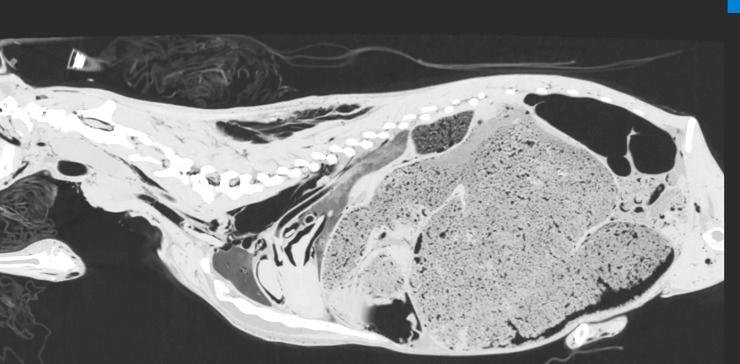

Evaluation of the usefulness of air as a negative contrast medium of blood vessels in goats in post mortem computed tomography (PMCT) and establishing the protocol with appropriate doses and timing of the contrast medium administration.

Thirty three goats were euthanized 10 to 300 min before the study. First, in 3 goats air was administered into the left or right common carotid artery at dose of 60, 100 and 120 ml/kg, and after each dose PMCT was performed in lateral recumbency. As the latter dose proved to visualize blood vessels best, following 30 goats were examined in the same manner but only with the use of air dose of 120 ml/kg. The quality of CT scans was evaluated independently by two board-certified radiologists.

RESULTS

In all studied animals the vascular system filled with air was clearly visualized on CT scans. In most of goats this amount of air revealed vessels smaller than 4 mm in diameter.

评估空气作为死后计算机断层扫描(PMCT)中血管负性对比介质的用途,并制定合适剂量和对比介质给药时间的方案。

33 只山羊在研究前 10 至 300 分钟被安乐死。首先,在 3 只山羊中,以 60、100 和 120 ml/kg 的剂量将空气注入左或右颈总动脉,每次给药后在侧卧位进行 PMCT。由于后一个剂量证明可以最好地显示血管,随后对 30 只山羊以相同的方式进行检查,但仅使用 120 ml/kg 的空气剂量。两名经过委员会认证的放射科医生独立评估 CT 扫描的质量。

结果

在所有研究动物中,血管系统都在 CT 扫描中清晰可见。在大多数山羊中,这种数量的空气揭示了直径小于 4 毫米的血管。